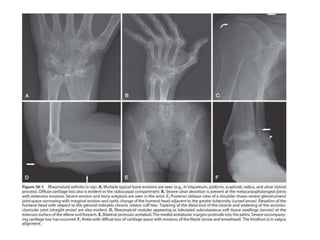

X-RAY

Characteristic findings on radiographs of Inflammatory

arthritis

may include:

•Soft tissue swelling,

•Chondrocalcinosis

•Joint effusion

•Juxta-articular osteopenia

•Symmetric loss of articular cartilage with joint space

narrowing

•Bony erosions- important markers of progressive

damage

X-RAY Characteristic findings onradiographs of Inflammatory arthritis may include: •Soft tissue swelling, •Chondrocalcinosis •Joint effusion •Juxta-articular osteopenia •Symmetric loss of articular cartilage with joint space narrowing •Bony erosions- important markers of progressive damage